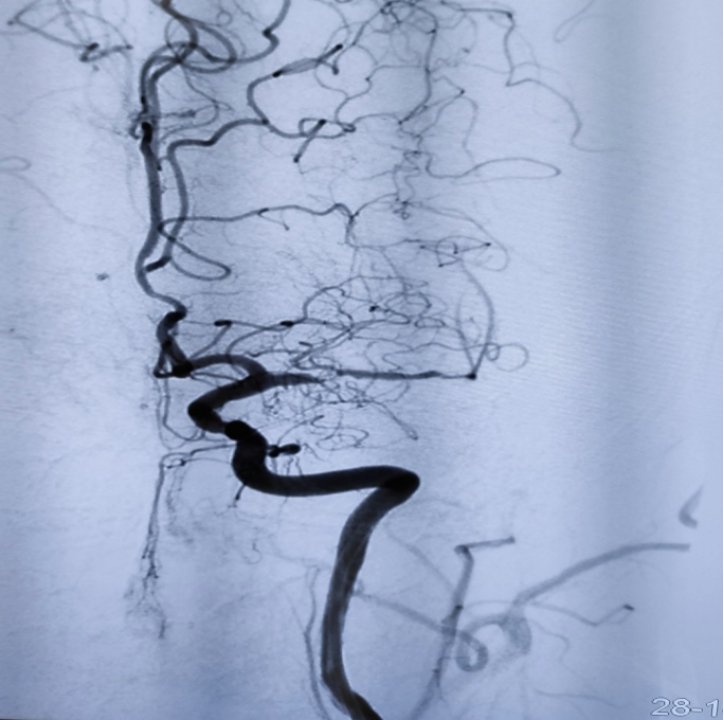

紅色箭頭提示大腦中動脈重度狹窄